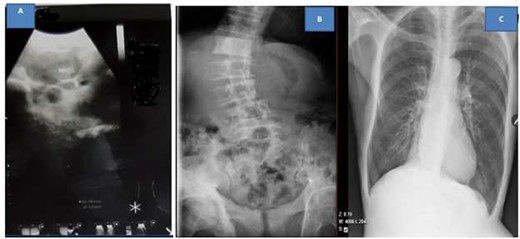

Abdominal ultrasound revealed ill-defined, heterogeneous prostate and paraaortic lymph nodes enlargement. The rest of the abdomen was normal. Ultrasound of the neck showed multiple left supraclavicular hypodense well-marginated masses with hyper vascularity. The largest mass was approximately 4.21 × 4.45 cm (Fig. 4A). KUB X-ray revealed extensive osteoblastic lesions involving the lumbosacral spine, pelvic bone and proximal part of the femur bilaterally (Fig. 4B). Chest X-ray was negative for metastasis (Fig. 4C).

Ultrasound of left neck showing supraclavicular mass (A), kidney, ureter and urinary bladder X-ray showing extensive osteoblastic lesions (B) and normal chest X-ray (C)